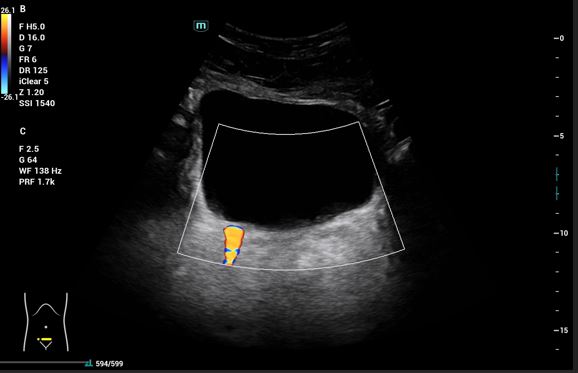

Pruebas complementarias: Sistemático de orina: microhematuria y ecografía abdominal: Riñones: (RD 11 cm, RI 12,09 cm), ecogenicidad, contornos y localización normales. RD: dilatación de la vía excretora Grado I dudosas imágenes de litiasis sin sombra acústica. No se evidencia líquido libre intrabdominal. Vejiga bien replecionada, jet ureteral bilateral simétrico, en trayecto del uréter derecho con Doppler color se observa artefacto de centelleo o efecto twinkling, que sugiere cálculo enclavado en unión vesicoureteral derecha.